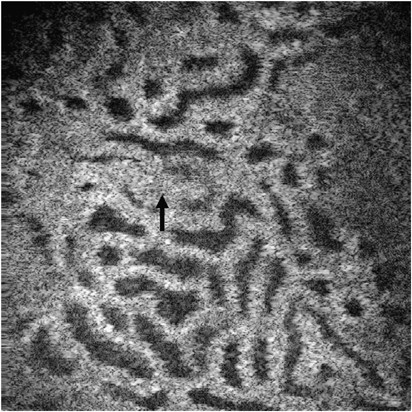

Figure 7

This en face OCT image of the superficial uriniferous tubules was taken 10 min following intravenous infusion of a single bolus of 1.0 ml containing 25% of mannitol. Note that the tubule walls are thinner and the tubule lumens are expanded when compared with control samples (see Figure 3). In the center of the field is a glomerulus (arrow). Image size: 750 × 750 μm.